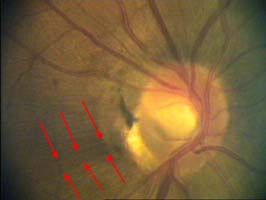

Modrá šipka - ukazuje plochu na sítnici, která obsahuje nervová vlákna. Sítnice je jemně proužkovaná, světlejší, cévy "jsou jako pod závojem". Červená šipka - ukazuje místo bez nervových vláken. Sítnice je tmavší, bez proužkování. Cévy jsou ohraničeny neobvykle ostře.